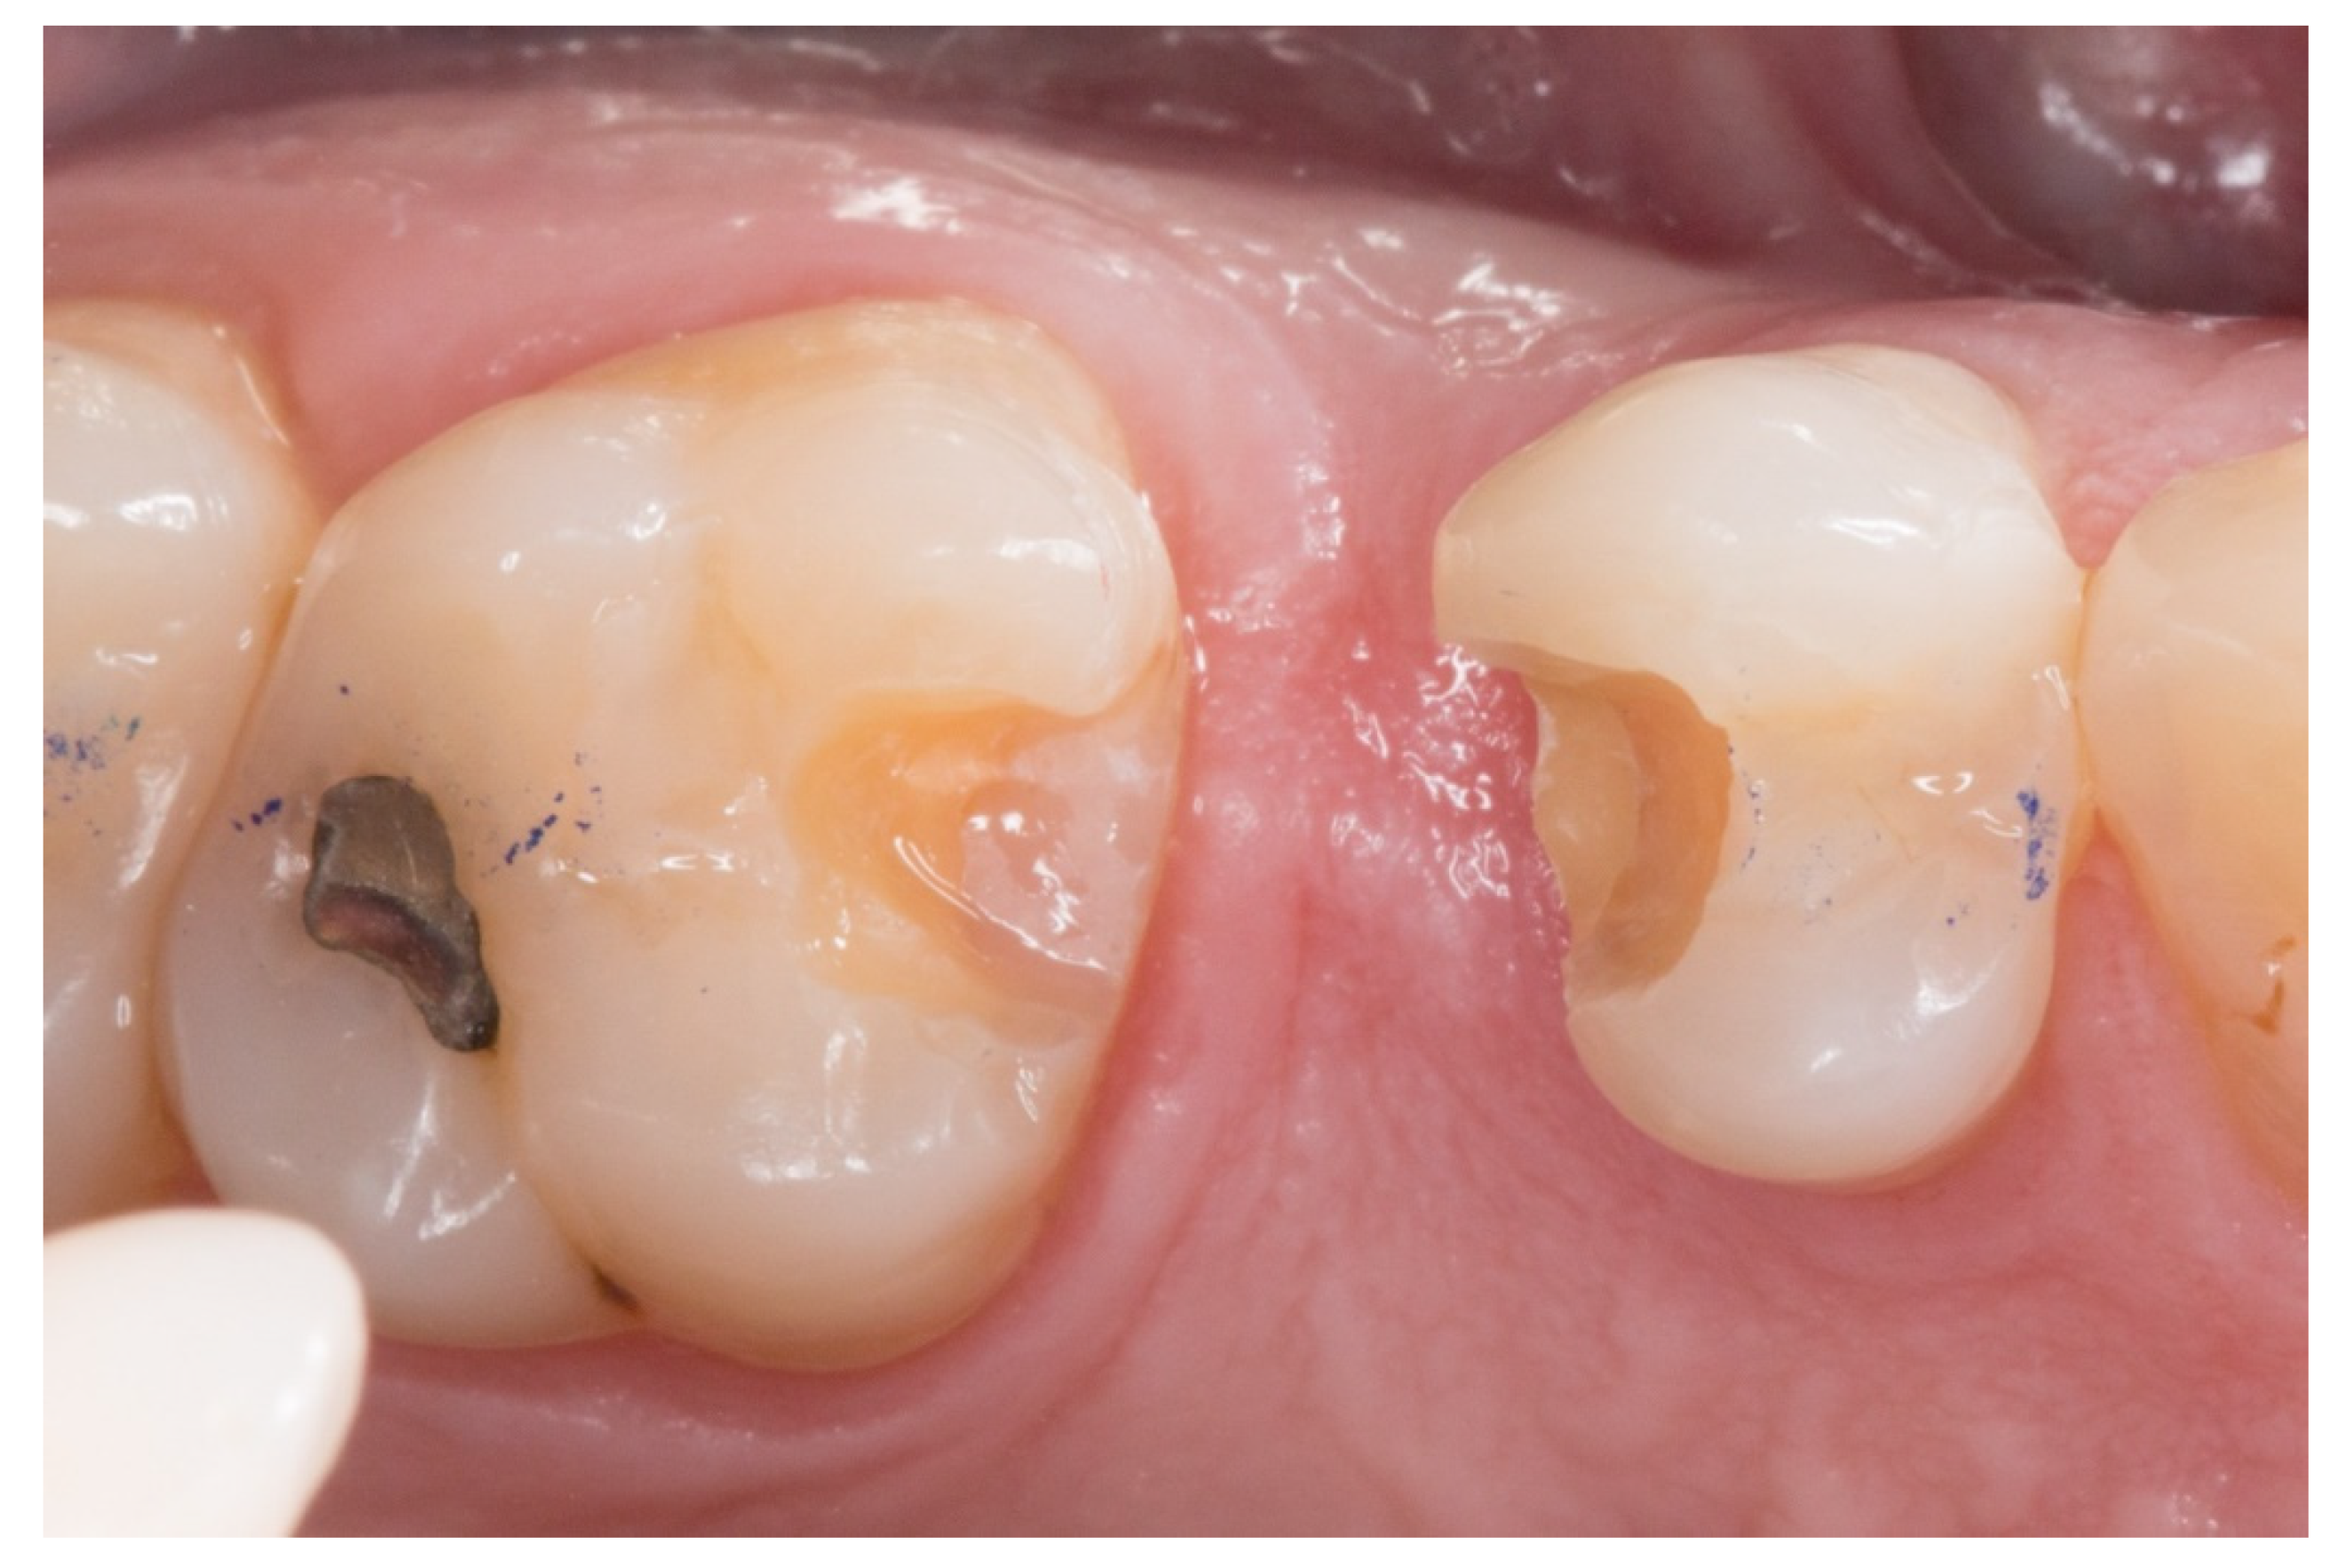

Figure 1.

A posterior maxilla edentulous space.

1. The new technique in “T” started once the silicone impressions of the patient were taken for both arches, and an interocclusal registration in the maximal intercuspation position was obtained, in order to prepare (on an articulator) the wax-up and the silicone keys for the tooth replacement [20]. Figure 1 represents the initial state of a case collected in the study.